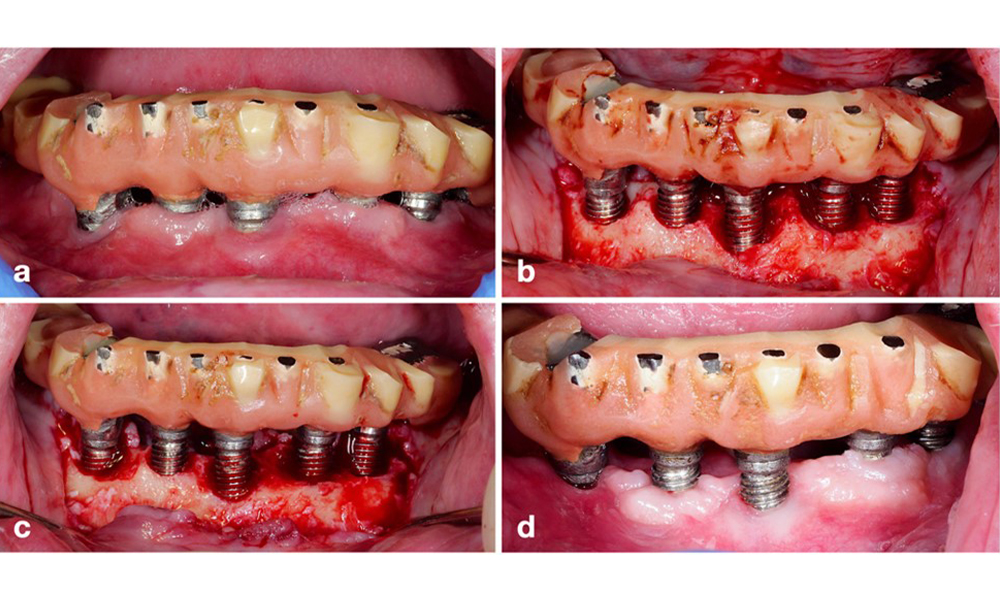

Die prothetische Restauration sollte bei einer nicht-chirurgischen ebenso wie bei einer chirurgischen Behandlung abgenommen werden, um einen besseren Zugang zur Implantatoberfläche zu ermöglichen. Die Wahl der chirurgischen Intervention (z. B. resektiv, rekonstruktiv oder eine Kombination) hängt von mehreren Faktoren ab: (1) Morphologie des Defekts (z. B. horizontal, Dehiszenz, intraossär oder eine Kombination) (Abb. 10), (2) Implantatoberfläche (also gedreht oder modifiziert/„rau“) und (3) Vorhandensein oder Fehlen einer ausreichend keratinierten und anhaftenden Schleimhaut.

Bei hauptsächlich horizontalen Knochenverlusten oder breiten Defekten mit begrenztem Knochenregenerationspotenzial sollte auf ein resektives Verfahren (also Gingivektomie und/oder apikal positionierter Lappen mit/ohne Knochenrekonturierung) zurückgegriffen werden (Abb. 11).

Für Implantate mit modifizierter Oberfläche und in Regionen, in denen eine Knochenregeneration unwahrscheinlich ist, sollte eine Implantoplastik in Erwägung gezogen werden. Dieses Verfahren beinhaltet die Entfernung des Implantatgewindes und die Glättung der mikrostrukturierten Implantatoberfläche mit rotierenden Instrumenten (Abb. 12). Dieses Verfahren erleichtert die umfassende Dekontamination der Implantatoberfläche und verbessert vor allem die postoperative Biofilmkontrolle (Bertl und Stavropoulus 2021; El Chaar et al. 2020; Geremias et al. 2017). Infolge mangelnder klinischer Evidenz wird die Rolle der Implantoplastik kontrovers diskutiert (Herrera et al. 2023; Ramanauskaite et al. 2021). Allerdings ließen sich die Bedenken im Hinblick auf Entzündungen durch die unvermeidliche Anlagerung von Titanpartikeln sowie auf ein erhöhtes Risiko von Implantatbrüchen infolge verminderter Implantatfestigkeit nicht bestätigen (Stavropoulos et al. 2019).

Für Implantate mit modifizierten Oberflächen und intraossären Defekten mit deutlich höherem Potenzial einer Re-Osseointegration wird ein rekonstruktives Verfahren empfohlen (Monje et al. 2023; Renvert et al. 2009). Dabei können autogener Knochen, Knochenersatzmaterial und/oder Membranen zum Einsatz kommen (Abb. 13) (Donos et al. 2023). Selbstverständlich erfordert ein rekonstruktives Verfahren eine gründliche Dekontamination der Implantatoberfläche. Sowohl Labor- als auch präklinische Studien zeigen, dass eine vollständige Entfernung des Biofilms von der Implantatoberfläche nicht möglich ist (Subramani & Wismeijer 2012). Daher wird für eine wirksame Dekontamination eine Kombination mechanischer und chemischer Maßnahmen empfohlen, wobei jedoch keine bestimmte Methode als überlegen gelten kann (Ramanauskaite et al. 2023; Wilensky et al. 2023). Laut mehrerer Laborstudien zeigen Luftpoliergeräte bei der Entfernung von Biofilm eine überlegene Wirksamkeit (Francis et al. 2022; Keim et al. 2019, Sahrmann et al., 2015). Dabei ist jedoch unbedingt zu beachten, dass intraoperatives Luftpolieren als Off-Label-Use gilt.